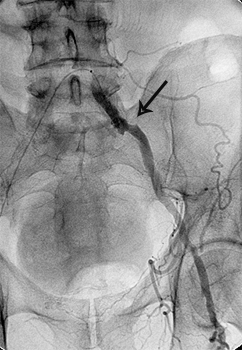

ЕМБОЛІЗАЦІЯ СУДИНИ

У деяких випадках потрібно припинити або зменшити кровотік по будь-якій судині, наприклад:

Послідовність виконання:

Катетер проводиться в судину, яку необхідно емболізувати. Положення катетера повинно виключати попадання емболізуючих речовин до інших судин. Через катетер в просвіт судини вводяться емболізуючі речовини або пристрої:

- спіралі: вводяться в артерію чи вену, припиняють кровотік у зоні їх установки (стволова емболізація)